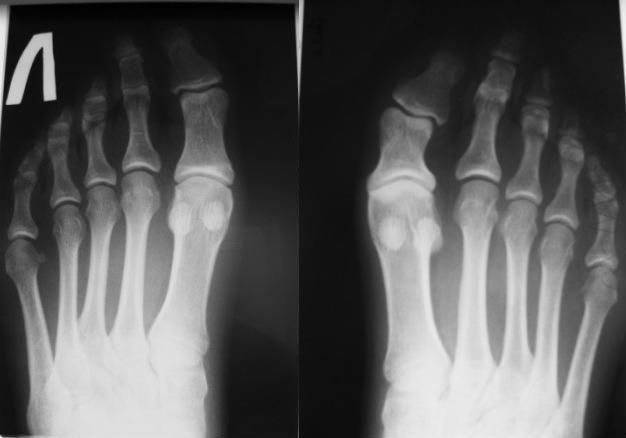

Рентгенограммы прилагаю.

Оптимально корригирующая "плюс" остеотомия с костной аутопластикой. Фиксировать тонкими спицами.

Что касается 2 пальца -так называемый "греческий" тип стопы - один из вариантов нормы. Его укорачивают при HALLUX VALGUS с сочатании с молоткообразной деформацией 2 пальца в зависимости от степени удлинения. Здесь молоткообразной деформации нет. Трогать по-моему не стоит.